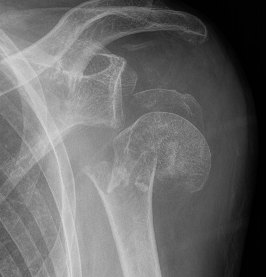

Severe comminuted proximal humerus fractures

100% displaced / off ended

Fracture - dislocations

Unreconstructable fracture - 4 part, comminuted, head spltting fracture